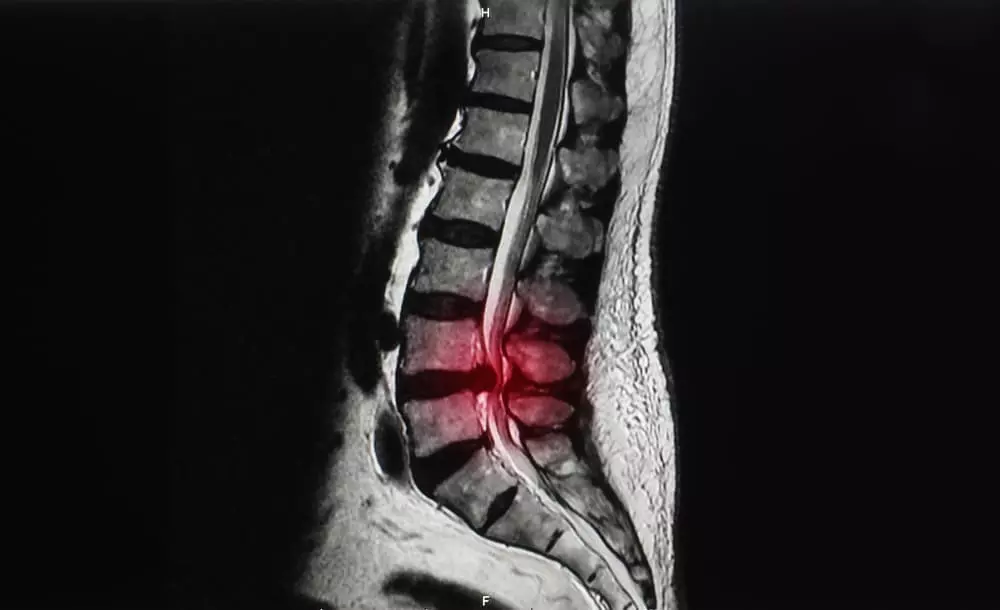

脊柱管狭窄症とは?

体を支える脊柱(背骨)は、一つ一つのブロックである椎骨が約32個から34個連結してできています。

その椎骨には穴が存在し、背骨として形成されたときには脊柱管という脊髄・血管が走る道が作られます。

その脊柱管が加齢などの原因でズレが生じ、椎骨と椎骨の間の間隔が狭まったときに発症するのが脊柱管狭窄症です。

椎骨と椎骨の間隔が狭くなると、内部を走っている脊髄や血管が上下から圧迫されます。

それにより、痛みやしびれ(坐骨神経痛)といった症状が現れます。